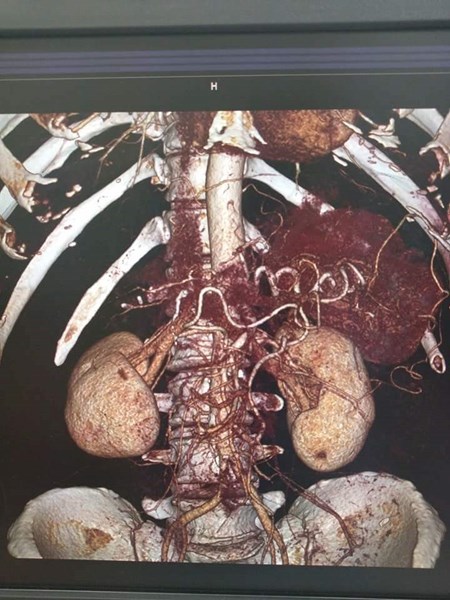

Иновативното е, че част от операцията е симулирана предоперативно на 3D медицинската маса за виртуални дисекции. На нея хирурзите са изучили анатомията на пациентката, дискутирали са най-подходящите входове за ръцете на роботизираната система в коремната кухина, за да се осигури оптимална позиция за балансирана работа на двата екипа. Подобен тип операции все още се извършват предимно чрез отворена хирургия, което води до голяма травма за пациента, поясниха от университета в Плевен.

Проф. Горчев коментира сложната операция така: "След клинично обсъждане на случая от екипите от хирурзи и гинеколози, взехме решение за извършване на тази изключително сложна операция с роботизираната система da Vinci Si, при която едновременно да се отстранят правото черво и матката на пациентката, т.н. задна тазова екзантерация. В същото време да се възстанови чревния тракт с ултраниска шевна линия на дебелото и правото черво."